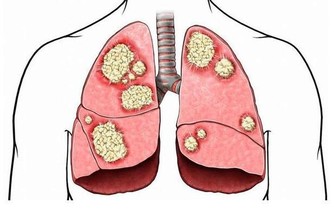

3、部分人因為受到腦膜的影響,出現腦袋疼痛情況。因為腦膜受到刺激之後會導致血管縮短,增加張力後出現疼痛。另外,腦部缺氧時也會出現噁心頭痛的情況,特別是到了高原地區,高原反應最常見的症狀就是頭暈噁心,需要及時吸取氧氣才能緩解。